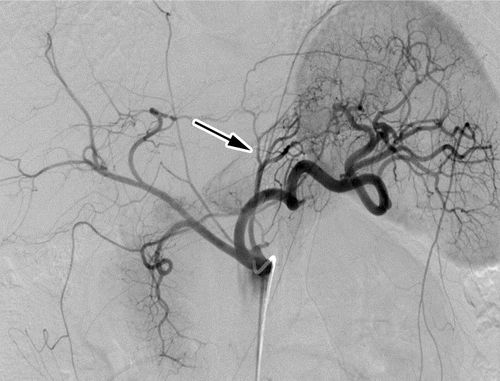

胃底动脉栓塞术通过影响胃底的内分泌功能来诱导患者的代谢变化,从而降低患者饥饿感,最终达到体重减轻目的(见图1)。为了评估胃底动脉栓塞术在重度肥胖患者治疗中的安全性和有效性,研究人员展开了一项开放、单臂、双中心的前瞻性研究—BEAT肥胖试验。

图1 胃底动脉栓塞术